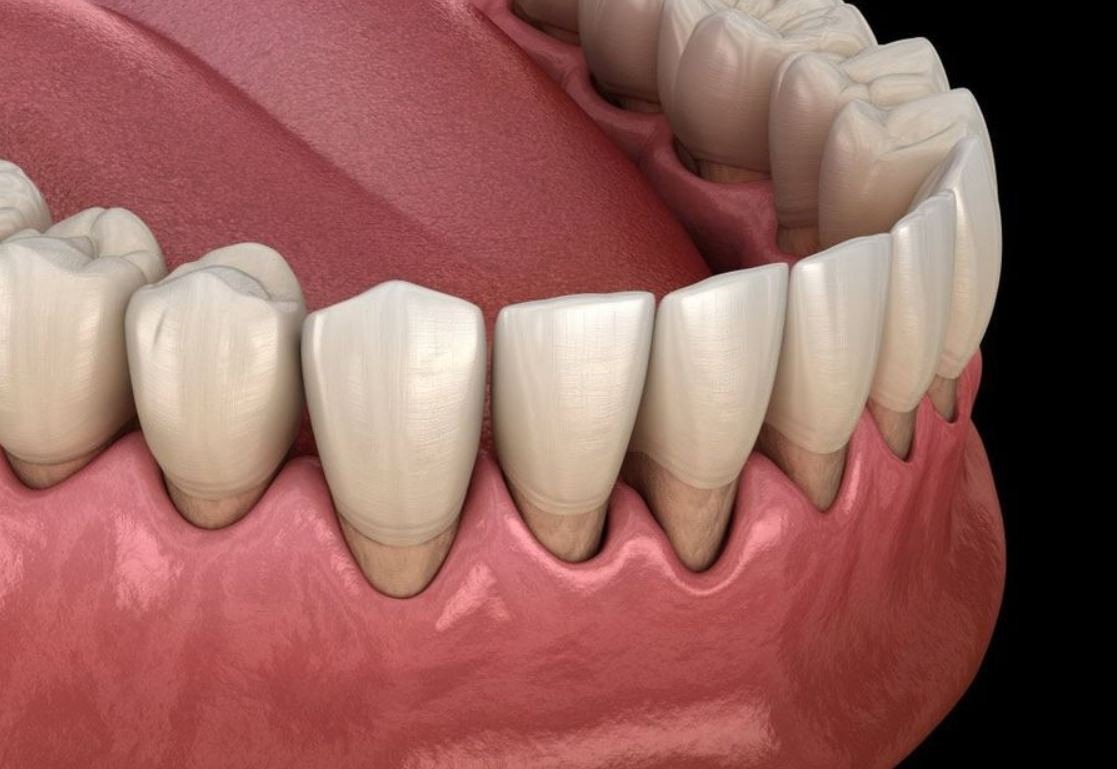

حفاظت از سلامت دندان: در مواردی که لثهها کشیده شده و ریشه دندانها بیشتر از حد بیرون آمده باشد و منجر به افزایش ریسک پوسیدگی دندان شود، انجام جراحی فلپ لثه میتواند به عنوان یک روش پیشگیری انتخاب شود.

تحلیل و فرسایش لثهها: در برخی موارد، جراحی باعث تحلیل و فرسایش بخشی از لثهها شده و نیاز به مراقبت و پیگیری دارد.

افزایش ریسک پوسیدگی دندان در ناحیه ریشهها: در برخی موارد، جراحی فلپ لثه باعث افزایش ریسک پوسیدگی دندانهای در ناحیه ریشهها میشود، بنابراین مراقبت دقیق از بهداشت دهان و دندان بسیار اهمیت دارد.